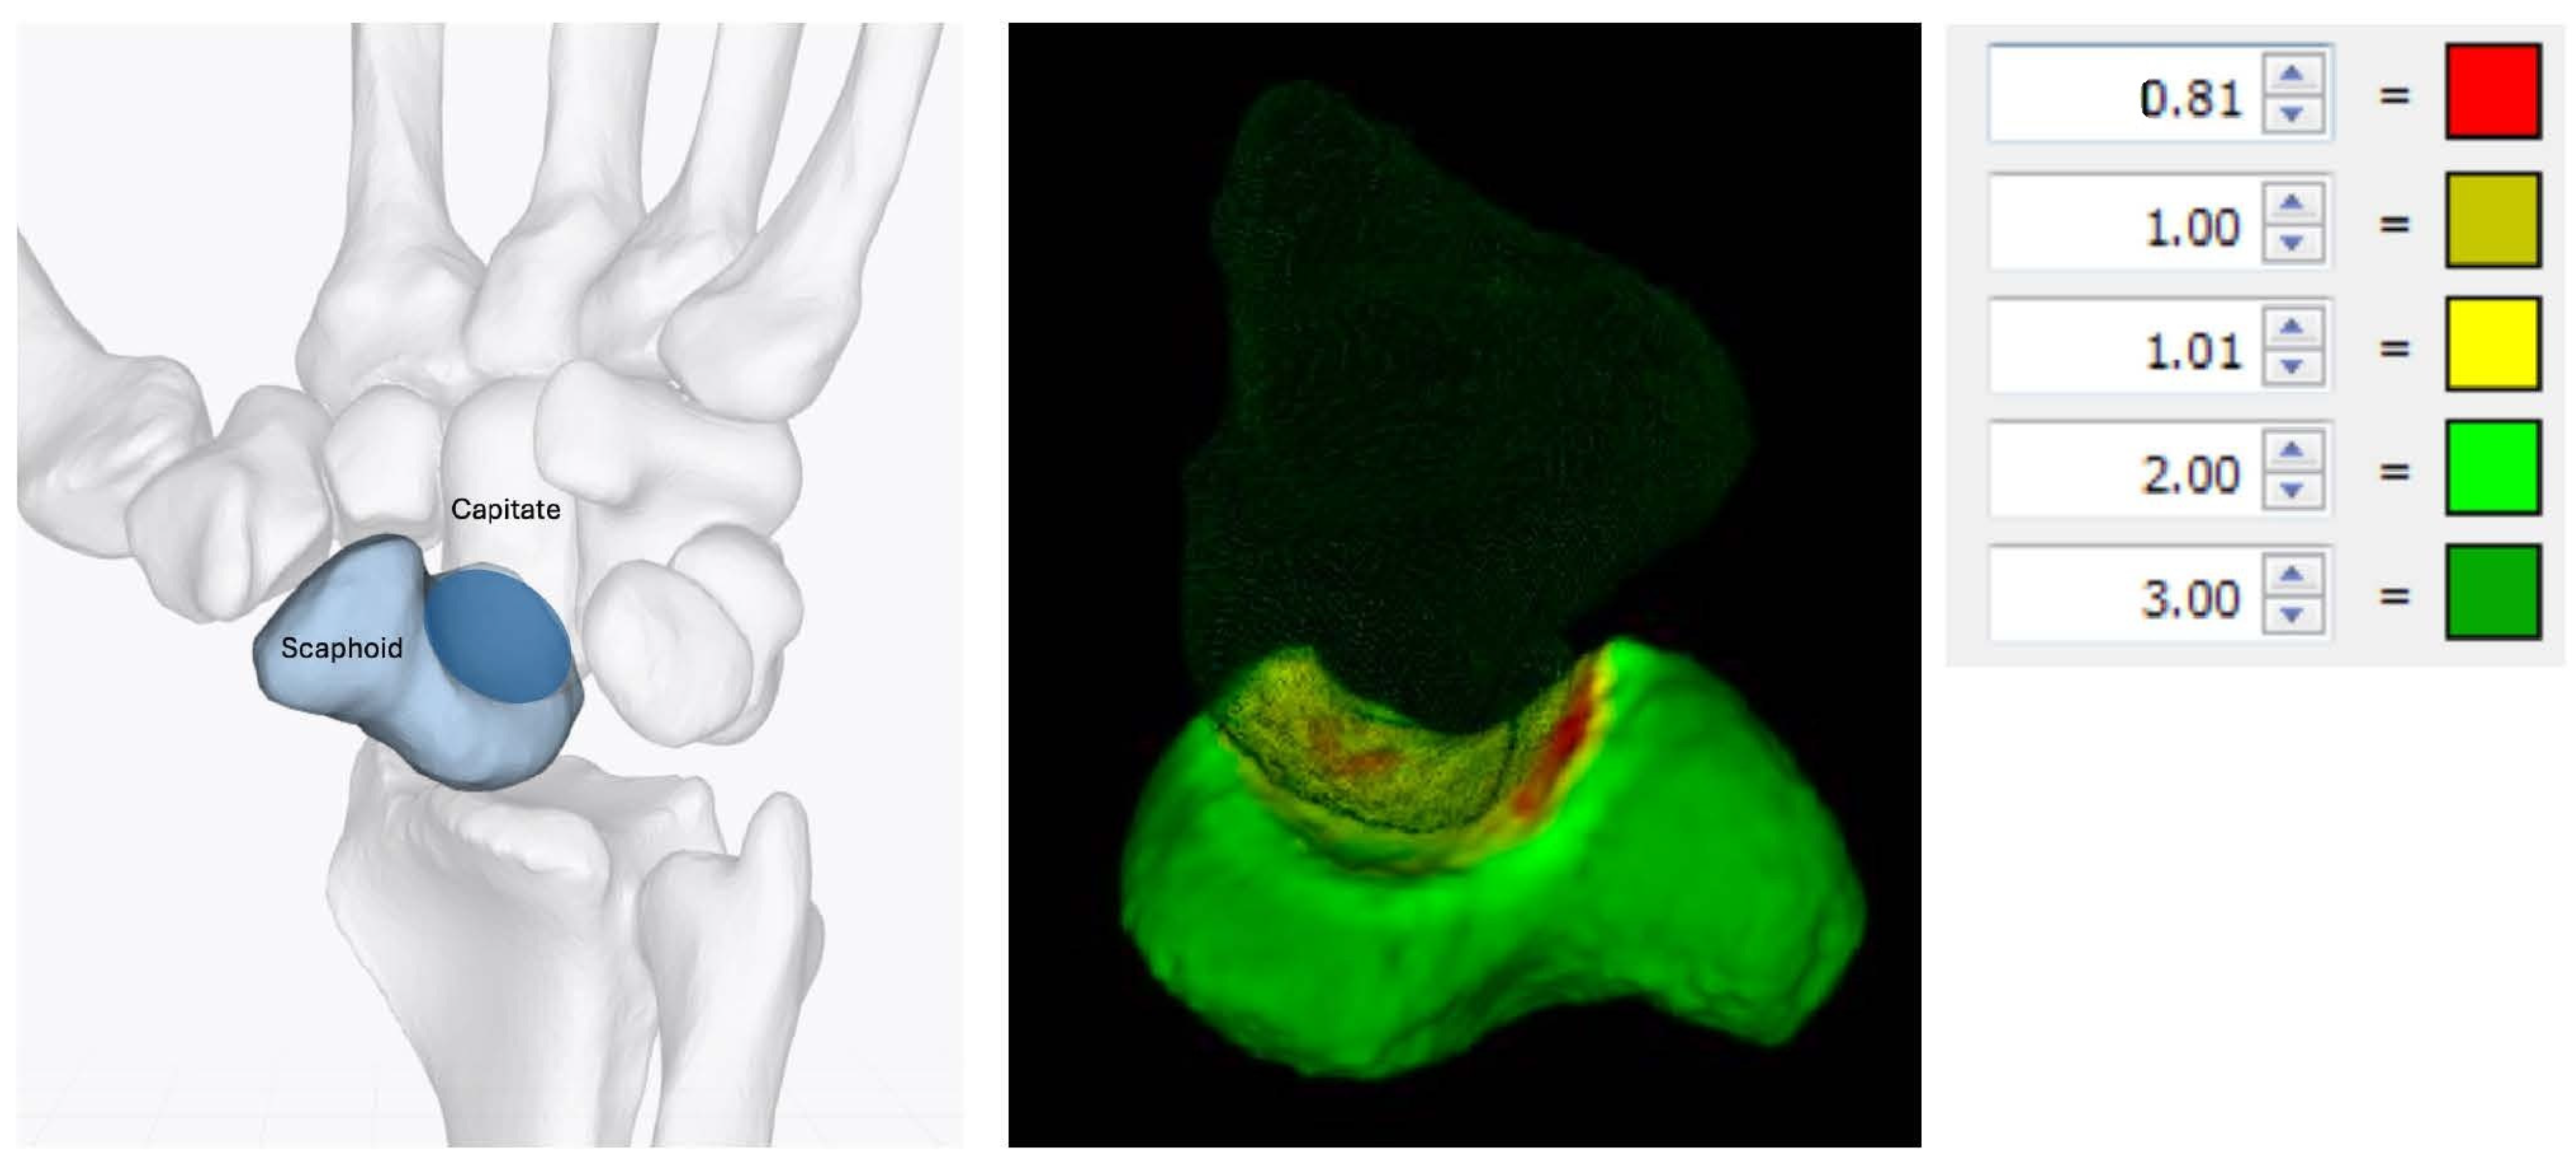

A native healthy forearm cadaver specimen—handled in accordance with the Human Research Act (Art. 36 and 37.1 HRA)—was donated with informed consent from the donor during their lifetime. This forearm was fresh frozen at −20 °C for >3 months, and ten CT-scans in the frozen and thawed conditions (completely thawed at 21 °C room temperature) were obtained using a standard wrist protocol (120 kVp; 120 mAs; slice thickness: 0.4 mm; voxel size: 0.17 × 0.17 × 0.2 mm) on a 2 × 64 row detector dual-source computed tomography scanner (Biograph 128®, Siemens Healthineers, Forchheim, Germany). The arms were scanned ten times in each condition to determine variability in the volume and shape measurements of the scaphoid due to the variability in the image acquisition and segmentation. Figure 1 shows a volume rendering and multiplanar reconstruction of a CT scan.

Figure 1. Volume rendering (a) and multiplanar reconstruction of the scaphoid ((b) = sagittal; (c) = coronal; (d) = axial).